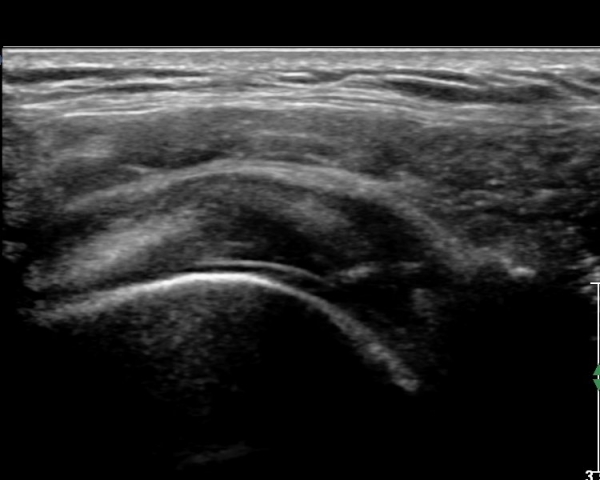

±ØÇ졂 Á¾´Ü¸é °Ë»ç¿¡¼­ Àá¾×³¶³» ¼ö¾×Àú·ù°¡ °üÂûµÇ°í(»çÁø 9) ÅÒÃËÀÚ¸¦ Á¶±Ý ³»ÃøÀ¸·Î

À̵¿ÇÏ´Ï  ±Ø»ó°ÇÀÌ ¼Ò½ÇµÇ°í ¼ö¾×Àú·ù°¡ °üÂûµÈ´Ù(»çÁø 10).

È¸Àü±Ù°³ Ⱦ´Ü¸é°Ë»ç¿¡¼­ ±Ø»ó°Ç ³»ÃøºÎ ºÎºÐ °á¼ÕÀÌ °üÂûµÇ°í(»çÁø 11) ŽÃËÀÚ¸¦ Á¶±Ý

¸»´ÜÀ¸·Î À̵¿ÇÏ´Ï ±Ø»ó°Ç ³»ÃøºÎ ÀüÃþÆÄ¿­ÀÌ °üÂûµÈ´Ù(»çÁö 12).